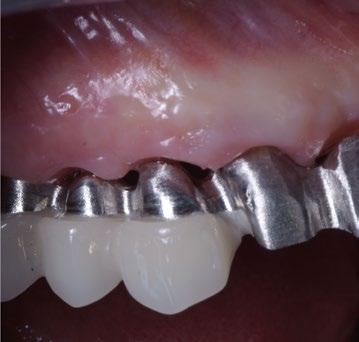

Fotos iniciales que muestran claramente el grave compromiso de la arcada superior debido a la enfermedad periodontal. Giovanni Zucchelli Alessandro Zucchelli Pietro Bellone

Curación después de la limpieza con provisional reforzado anclado en los elementos residuales 17, 15, 11, 21, 23, 24, 25.